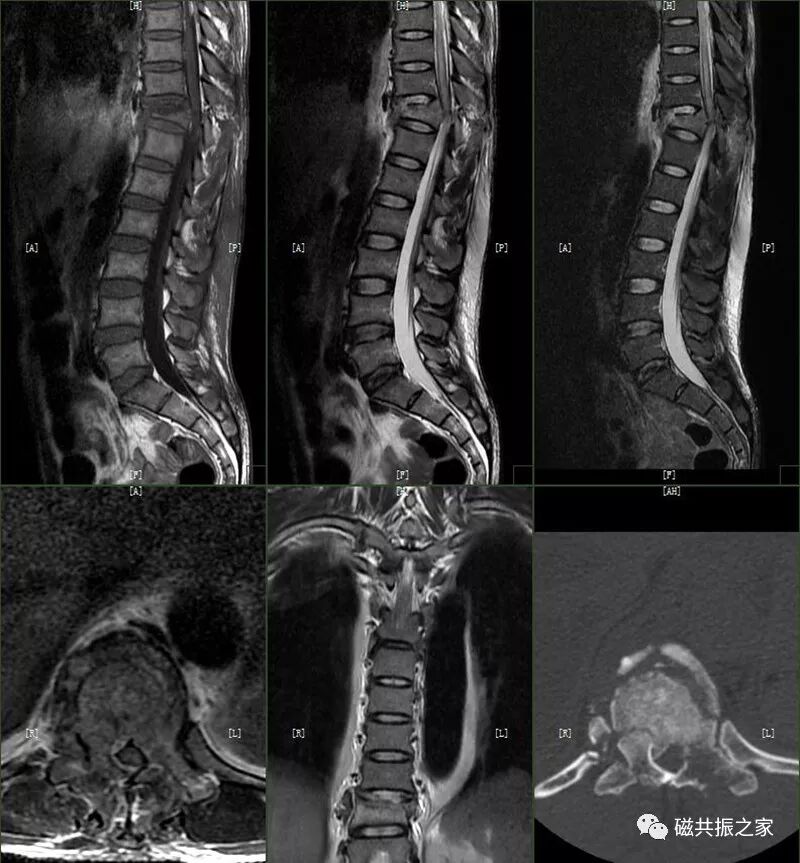

1.循环系统:主动脉夹层和胸腹主动脉瘤(破裂)、大量心包积液(血)。D:-CT-MR室资料新闻稿文件夹微信图片_20211127090743.jpg腰椎MRI扫描时发现的巨大腹主动脉瘤

4.骨关节:颈椎多发严重骨折;椎体爆裂性骨折并脊髓损伤;骨盆多发骨折;四肢多发开放性骨折。

图片D:-CT-MR室资料新闻稿文件夹微信图片_20211127090833.jpg椎体爆裂性骨折并脊髓损伤